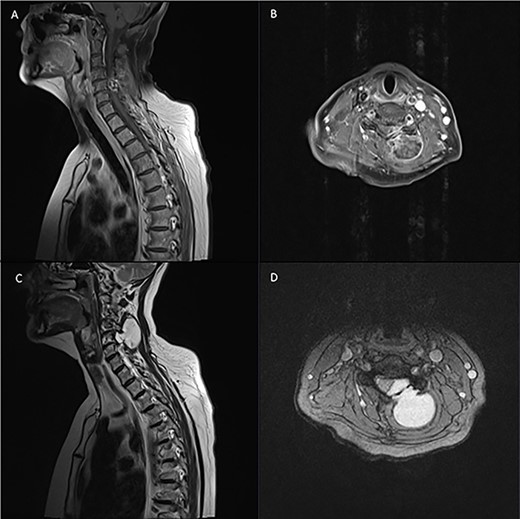

Pre-operative T1 post Gadolinium and T2 weighted MRI: left-sided extra-axial mass at C5/6 with heterogenous enhancement on T1 and hyperintense on T2. Moderate compression of the spinal cord and invasion into surrounding soft tissue.

Diagnostic spinal imaging showed a large mixed cystic solid destructive bony lesion arising from the bony elements at C5 with heterogenous enhancement (Fig. 3). A chest/abdomen/pelvic CT did not identify any further lesions.